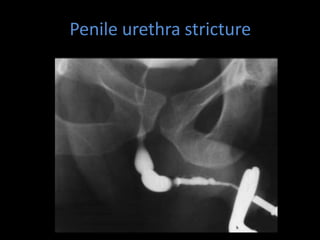

Penile urethra stricture